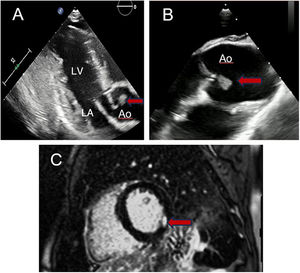

A 16-year-old boy with a history of ulcerative colitis presented at our hospital complaining of crushing retrosternal pain at rest. He was afebrile and the physical examination was normal. The electrocardiogram showed ST-segment depression in the precordial leads during episodes of pain (figure 1A, circle); the depression disappeared with the pain (figure 1B). Troponin I levels ranged from 341 to 6162 ng/L. Transthoracic echocardiography showed inferolateral hypokinesis with a left ventricular ejection fraction of 50% and a mobile vegetation measuring 15 mm in diameter attached to the aortic side of the right coronary cusp (figure 2A, arrow; LA, left atrium; Ao, aorta; LV, left ventricle). Presence of the vegetation was confirmed by transesophageal echocardiography (figure 2B, arrow). Serologies and blood cultures, including those for fastidious microorganisms such as HACEK bacteria (Haemophilus, Aggregatibacter, Cardiobacterium, Eikenella, and Kingella), were negative. Cardiac magnetic resonance imaging showed mild hyperintensity and late gadolinium enhancement in the inferolateral subendocardial layer (figure 2C, arrow).